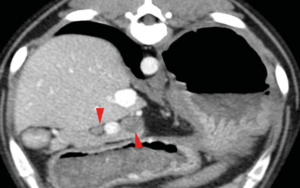

En casos de obstrucción biliar se debe considerar la duodenotomía y la colocación de un stent temporal en el colédoco, que sale al duodeno a través de la papila duonedal mayor, mientras se resuelve la compresión temporal por el absceso/inflamación (imágenes 2A y 2B). La colocación de stents de colédoco también se ha descrito en gatos.25-27 En esta especie, durante este procedimiento se debe tener cuidado de no cateterizar el conducto pancreático debido a la conexión anatómica entre el conducto pancreático y el conducto biliar común.28

Imágenes 3A – 3I. Secuencia de imágenes quirúrgicas en un perro (con las imágenes del TC), durante una pancreatectomía parcial del lóbulo izquierdo y cuerpo del páncreas, usando un sellador vascular/tisular, por carcinoma pancreático.